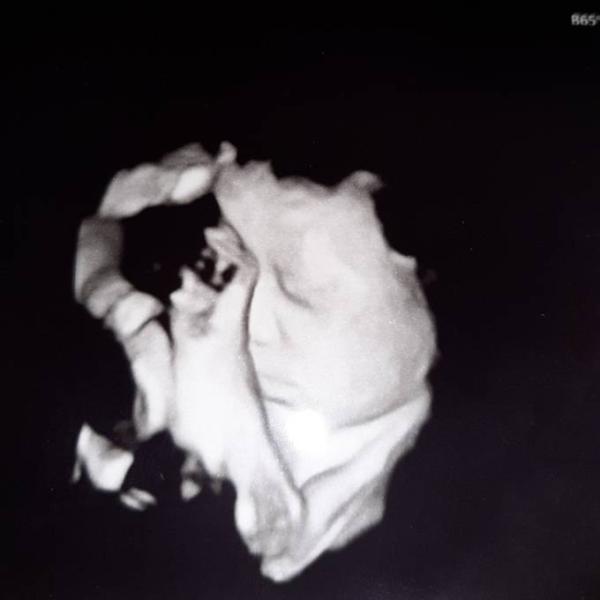

Gestern bei 34+6 waren wir wieder beim Ultraschall Und unsere süße Maus ist zum verlieben Mittlerweile wiegt sie ca. 2460g und entwickelt sich sehr gut. Alles zeitgerecht. Zwischen durch hat sie gelächelt und uns die Zunge rausgestreckt Und dann konnte man sehen wie sie das Fruchtwasser trinkt. Mein Gebärmutterhals ist schon auf 1,8cm verkürzt aber mittlerweile Entwarnung das sie zu früh kommen wird. Mit dem Magnesium haben wir das ganz gut in den Griff bekommen so, dass ich es langsam wieder absetzen soll Ich wünsche euch allen einen schönen Nikolaus Und hier noch ein Bild von ihr

Bild zu Gestern wieder Untersuchung gehabt - Forum für Januar - Mamis